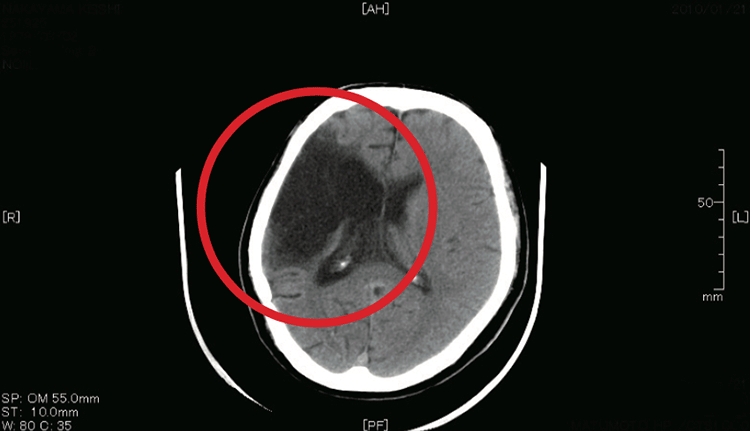

心房細動になると左心房内で血流がよどむことから、左心耳(さしんじ)内に血栓(けっせん)(血の塊(かたまり))を作りやすく、脳梗塞の原因となります(図1)。このため洞調律(※1)に復帰させるリズムコントロールや左心耳を閉鎖することによって、脳梗塞や血栓塞栓症を予防することが重要となります。